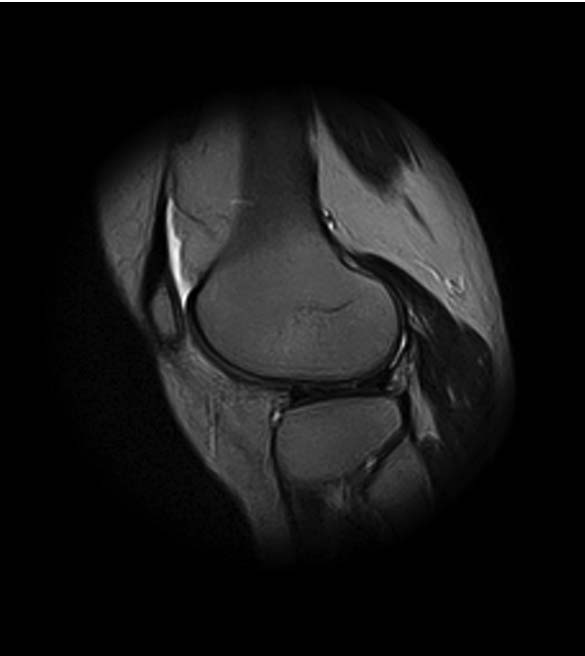

1. травма 5 лет назад - "ударилась коленом", с тех пор боли в суставе

3. стандартные рентгенограммы с небольшими изменениями - сужение

медиальной суставной щели

4. вес пациентки 80 кг, рост 165

5. сустав клинически стабилен